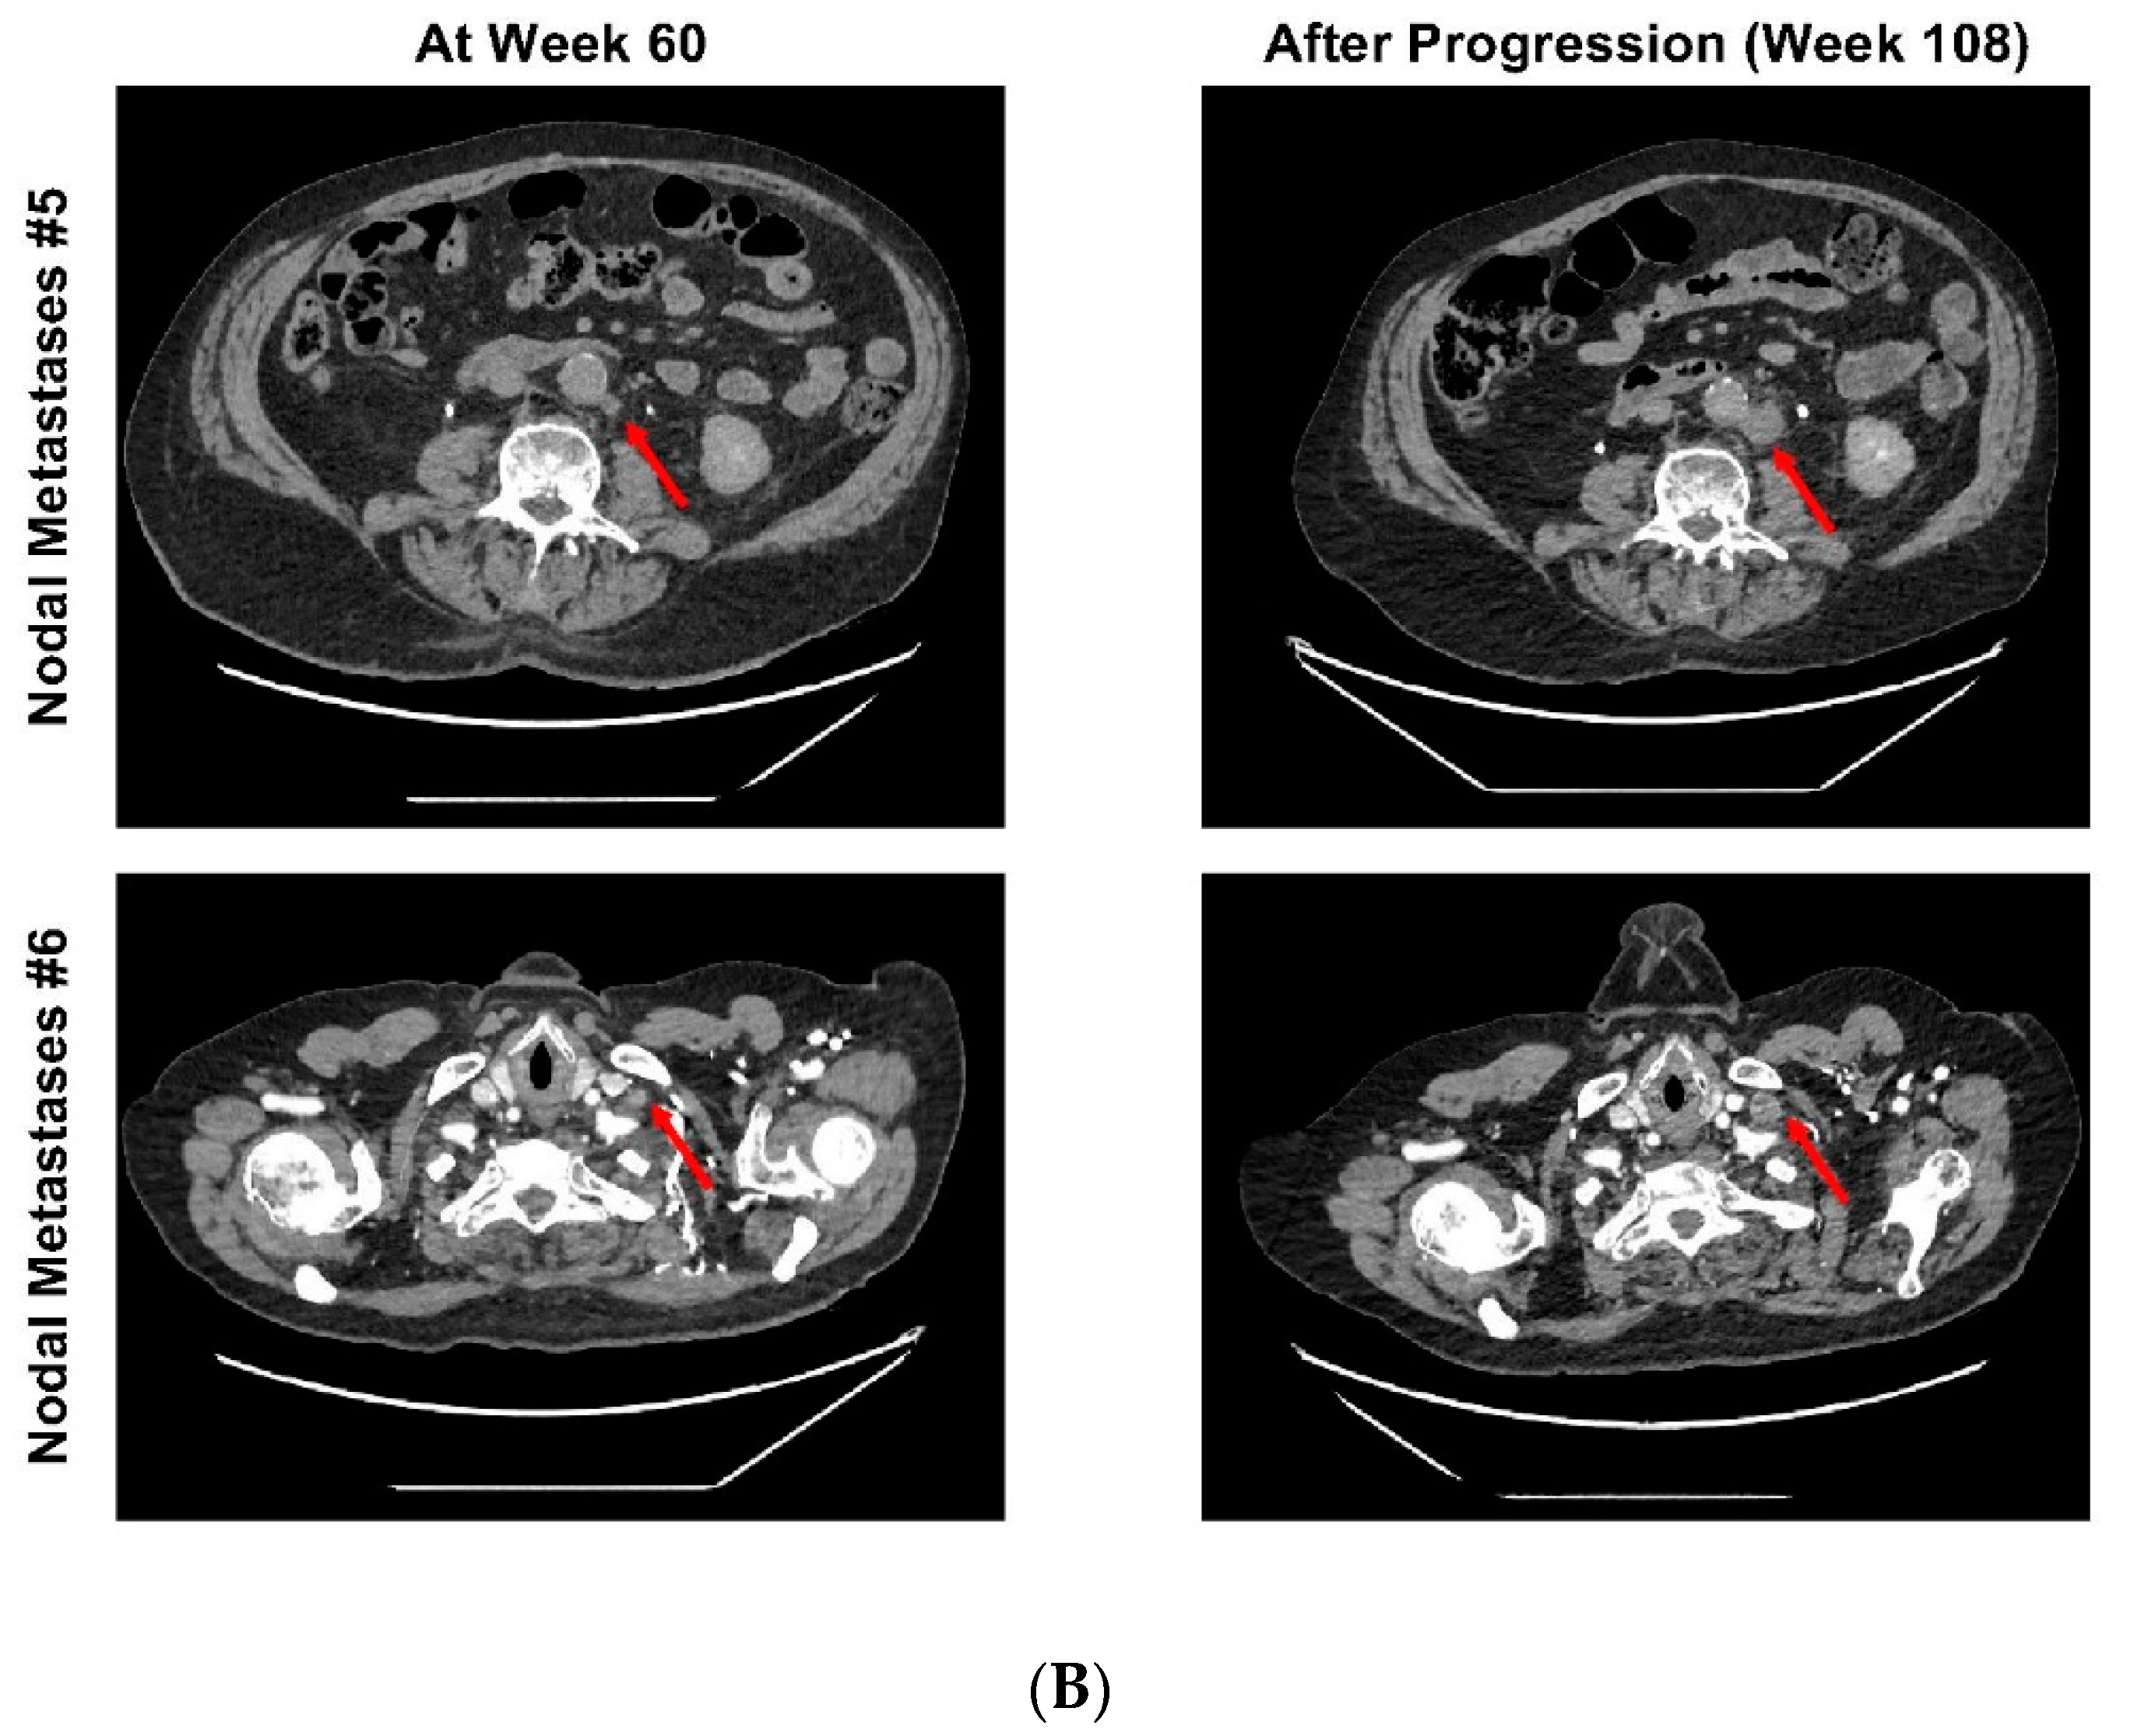

2. Case Report